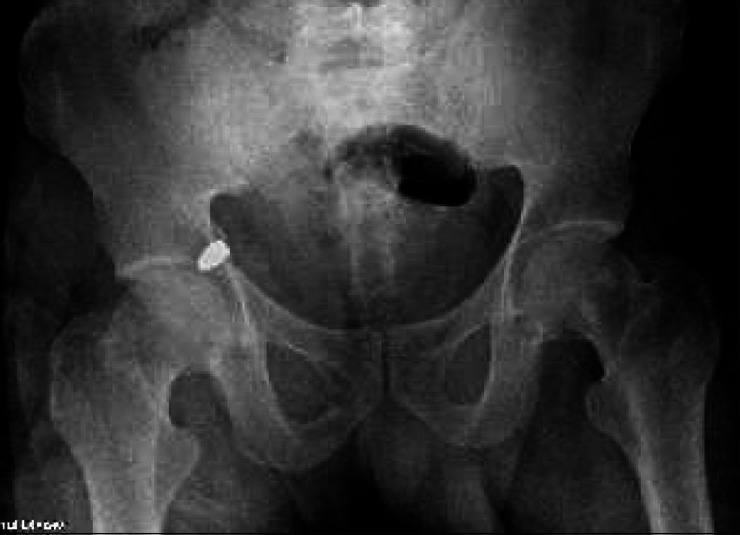

与标准的开放式关节切开术相比,髋关节镜已被证明能以微创方式进入髋关节。关节镜在诊断和治疗髋关节疾病方面的应用在不断发展。本研究描述了一个在关节镜下取出低速枪伤子弹的病例。患者的枪伤进入腹部,穿过小肠和乙状结肠,然后穿透膀胱,最后进入髋臼内侧壁。在对内脏进行手术修复后,使用标准关节镜门户和骨折台从髋关节中取出了子弹。决定使用关节镜的原因有很多。最重要的是需要最大限度地减少软组织剥离,这是取出子弹所必需的,同时又不影响耻骨上区域之前的伤口。在进行手术之前,还考虑了子弹碎片和移位的潜在风险,以及可能出现的腹腔隔综合征。关节镜手术可以充分检查关节表面、冲洗关节并取出异物,同时避免了侵入性关节切开术及其相关的发病率和软组织破坏。这种手术技术为这名患者带来了非常满意的结果,并为其他遇到类似损伤模式的外伤患者提供了范例。对于有髋关节镜手术经验的外科医生来说,这种手术可以安全、快速地进行,而且并发症极少。

Hip arthroscopy has been shown to offer minimally invasive access to the hip joint compared with standard open arthrotomy. The use of arthroscopy for diagnosing and treating disorders about the hip continues to evolve. This study describes a case that involves arthroscopic removal of a bullet from a low-velocity gunshot wound. The patient sustained a gunshot wound that entered the abdomen and traversed the small bowel, sigmoid colon then penetrated the urinary bladder before ending up in the medial wall of the acetabulum. After surgical repair of the viscus, the bullet was retrieved from the hip joint using standard arthroscopic portals and a fracture table. A number of issues led to the decision to use arthroscopy. Most importantly was the need to minimize soft tissue dissection, which was required to access the bullet, without interfering with previous wound at the suprapubic area. The risks of potential bullet fragmentation and migration, as well as a possible abdominal compartment syndrome were considered before proceeding. Arthroscopy allowed adequate inspection of the articular surface, irrigation of the joint, and removal of the foreign body while avoiding an invasive arthrotomy with its associated morbidity and soft tissue disruption. This surgical technique afforded a very satisfactory outcome for this patient and serves as a model for others when encountering a similar injury pattern in a trauma patient. It is a procedure that can be performed safely, quickly, and with minimal complications for surgeons with experience in arthroscopy of the hip joint.